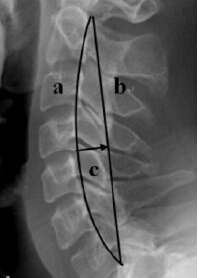

矢状面示颈椎生理曲度后凸,椎体轻度变扁,边缘毛糙变尖信号正常,t2wi示多个椎间盘信号减低,c5/6,c6/7椎间隙平面蛛网膜下腔受压,形成弧形压迹,t1w1示c5/6,c6/7间盘后缘呈锤